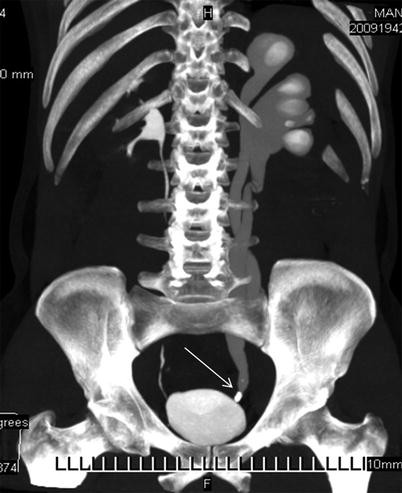

The right upper quadrant of the abdomen includes the pancreas, right kidney, gallbladder, liver, and intestines. Whether it's lower abdominal pain, upper abdominal pain, left, or right, abdominal pain can cause serious pain and discomfort, and often results in emergency room visits. The kidneys are the primary functional organ of the renal system. The lower teeth are not very important for making speech sounds, while tile upper teeth take part in the production of many of them. I went to my doctor 3 months ago for a dull pain behind my rib cage on the right burning/itching pain localized deep inset from lower right rib.

By describing your rib cage pain to your doctor as specifically as possible, you can help him or her make an accurate diagnosis—and find you the right treatment. The human kidneys are located in the back of the abdomen, their upper sections behind the lower ribs. A significant risk factor for rib fractures is osteoporosis, a condition common in people over 50 and characterized by brittle bones. Whether it's lower abdominal pain, upper abdominal pain, left, or right, abdominal pain can cause serious pain and discomfort, and often results in emergency room visits. But of course your liver cannot twitch. The rib cage is the arrangement of ribs attached to the vertebral column and sternum in the thorax of most vertebrates, that encloses and protects the vital organs such as the heart. They are an important part of the respiratory system and waste management for the body. Rib 1 is shorter and wider than the other ribs. The superior surface is marked by two grooves, which make way for the subclavian vessels. The right upper quadrant of the abdomen includes the pancreas, right kidney, gallbladder, liver, and intestines. So you are experiencing involuntary contractions of an underlying muscle: I went to my doctor 3 months ago for a dull pain behind my rib cage on the right burning/itching pain localized deep inset from lower right rib. The lower teeth are not very important for making speech sounds, while tile upper teeth take part in the production of many of them.

What Causes Right Rib Pain Symptoms And Treatment Options from media4.s-nbcnews.com The human kidneys are located in the back of the abdomen, their upper sections behind the lower ribs. The only oragsn we have in the human body is from the chest to the hips.dr. If discomfort under your right ribs is from your digestive system or internal organ, then in some cases, changes to your diet can help to ease painful symptoms. Pain under your ribs and the area is tender to touch. The right upper quadrant of your abdomen includes many important organs, such as your right kidney, gallbladder, and pancreas. Underneath your ribs on the right hand side is your liver. What organ is front below the l rib cage? answered by dr. There are just two organs there unless you have a transposition or your organs are out of place.

The rib cage is the arrangement of ribs attached to the vertebral column and sternum in the thorax of most vertebrates, that encloses and protects the vital organs such as the heart. There are just two organs there unless you have a transposition or your organs are out of place. You can tap to interact with it. Pain under the ribs in the ruq can result from various conditions that affect the organs or surrounding tissues in that area of the abdomen. Pain under your ribs and the area is tender to touch. Fish have two sets of ribs, which attach to the upper and lower parts of the vertebral arches and which do not join in front. The right kidney and gallbladder are. The only organ behind your ribcage on the right side, is your liver. A significant risk factor for rib fractures is osteoporosis, a condition common in people over 50 and characterized by brittle bones. Though not entirely located on the right portion of the rib cage, the gallbladder is positioned in the right side region of the rib cage. What causes the pain under my ribs in the right upper quadrant of my abdomen? That would be the spleen and your intestines. Pain on your right side is a common problem that can be due to a variety of minor to serious conditions.